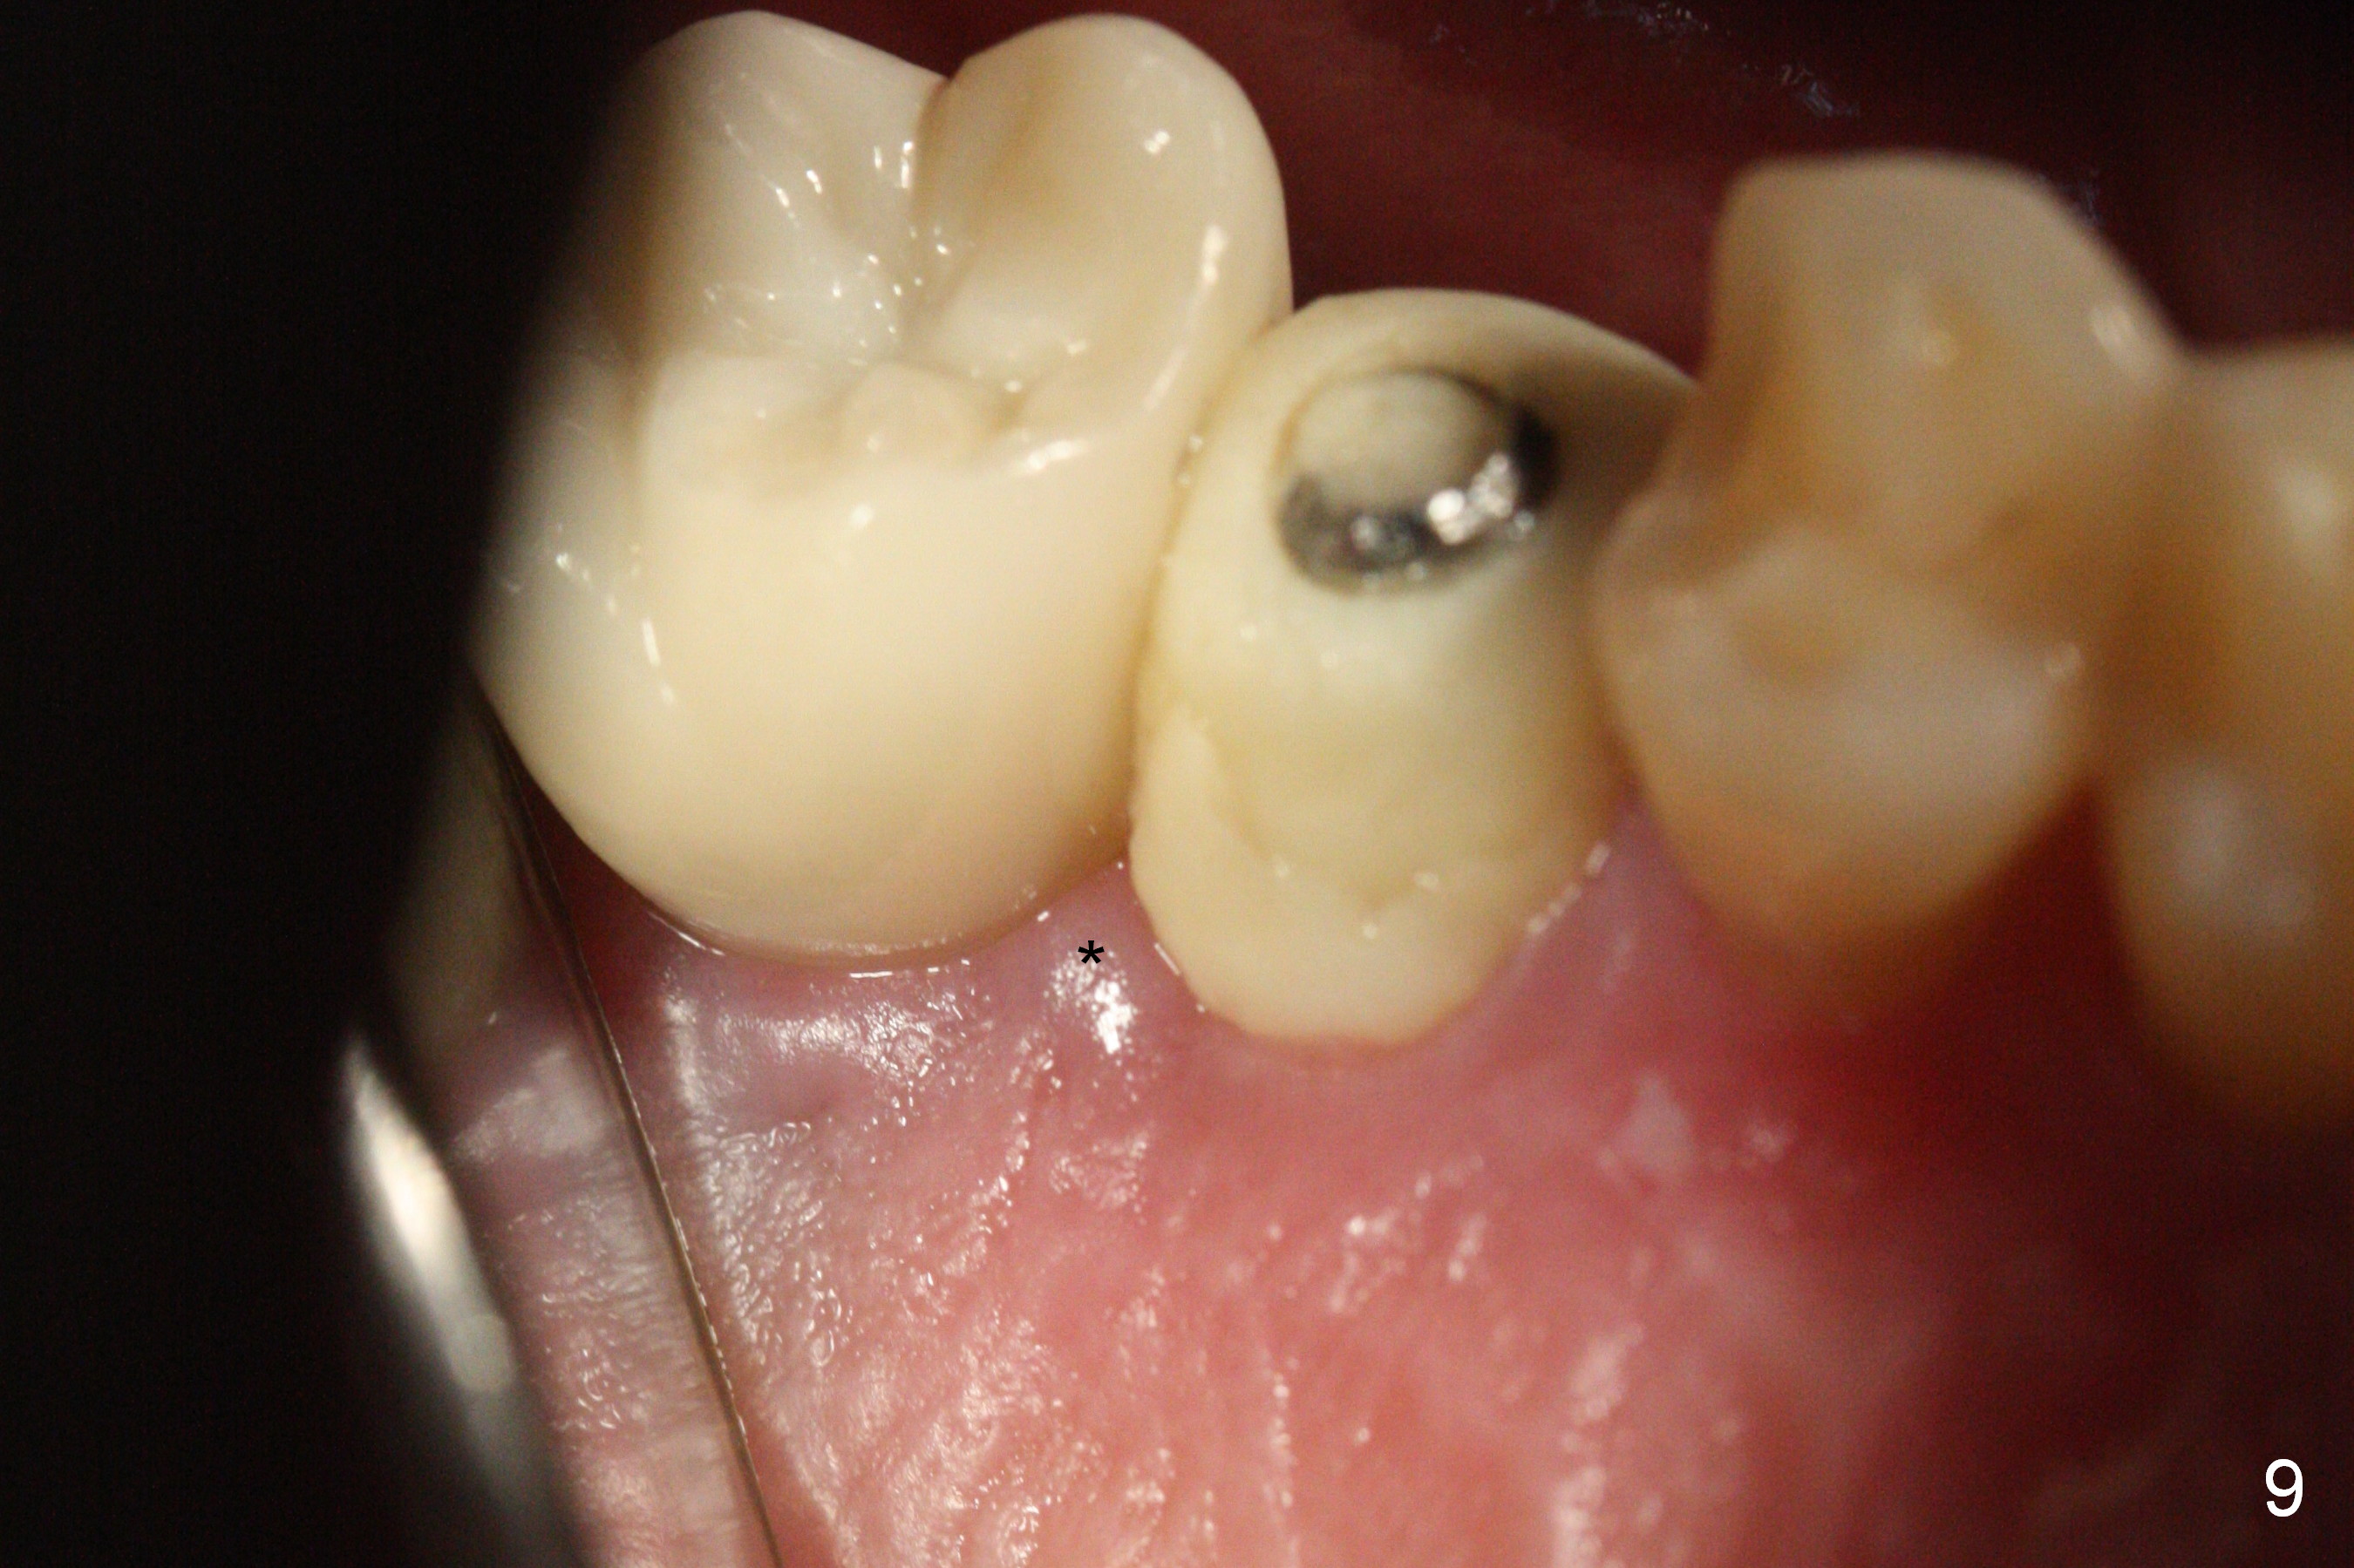

The distal papilla reforms buccally (Fig.8 *) and palatally (Fig.9) 4 months postop.  It appears that the 4 mm cuff of the pair abutment (Fig.10 >) is apical to the mesial crest (*).  The distal coronal implant threads seem to be covered by bone graft (Fig.11 <).  Therefore pair abutments with 5 mm or more cuff are required in cases of the uneven bone.   Implants have to be placed deep.  CT taken 3 months post cementation (10 months postop) shows that the implant is placed in the middle of the alveolus without apparent thread exposure.  CT taken 1 year and 8 months post cementation (Fig.13) shows that the implant is placed in the middle of the alveolus without apparent thread exposure, as compared to those at #2 and 3, which are placed buccal (B).